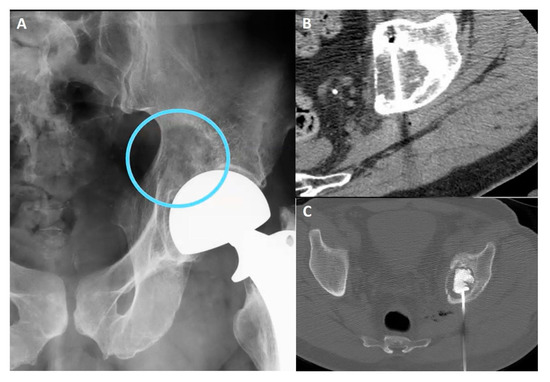

- Transflap: Useful in the case of early local tumor recurrence, in patients who underwent previous surgery, and myocutaneous flap reconstruction (Figure 4). The myocutaneous flap is usually devoid of significant vascularity and vital structures and presents a safe trajectory once it has been grafted [13].